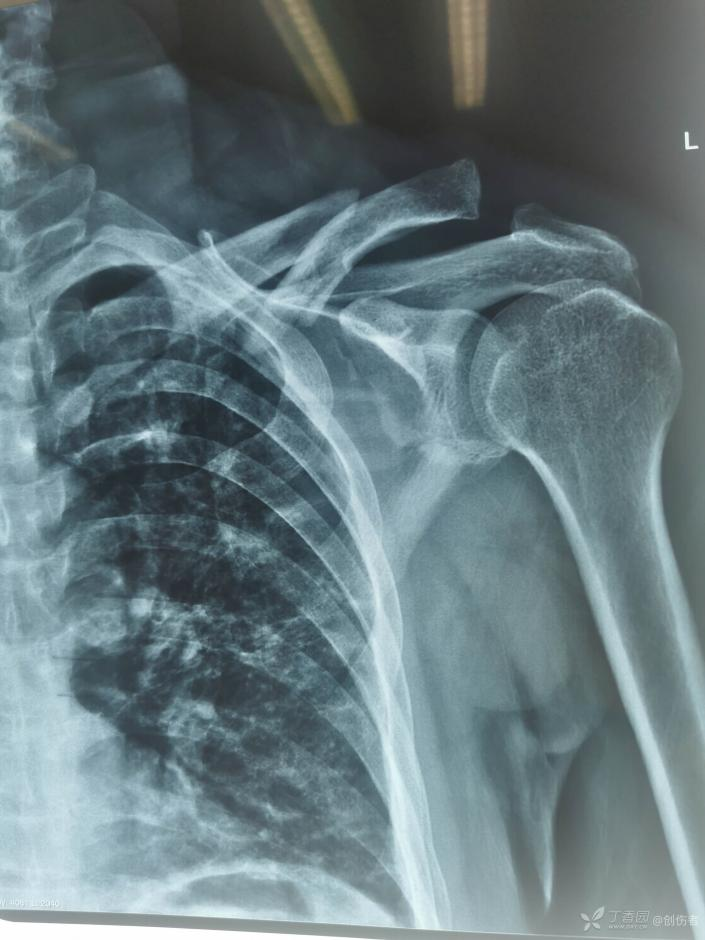

锁骨骨折大家一定都觉得很简单,但锁骨骨折也有一个并不少见的坑,看看下面的病例:

这个锁骨骨折简单吗?简单!做不就完了吗?

这个锁骨骨折简单吗?另一位网友分享:

等下,拍个双侧对比看看,锁骨骨折合并肩锁关节脱位,还好术前发现了 ……

这样的病例少吗?还真不少,一搜一大把!

6.8% 的锁骨中段骨折患者伴有同侧肩锁关节脱位。这个坑也不能踩啊!